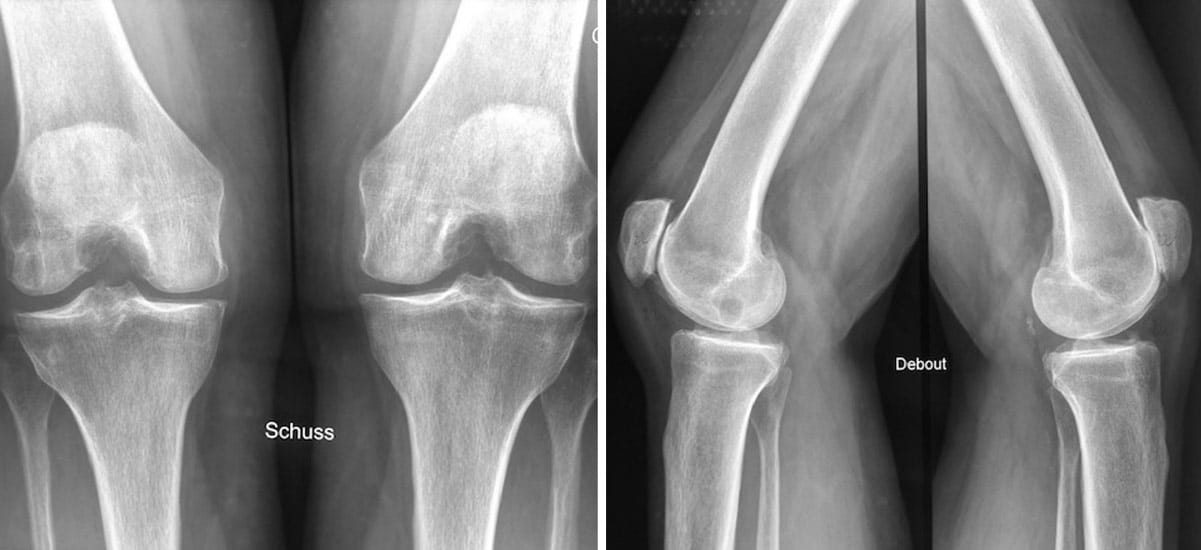

La radiographie

C’est une technique d’imagerie par transmission de rayons X. Ces rayons pénètrent la matière et permet d’obtenir une image dont le contraste dépend des structures traversées.

En orthopédie, la radiographie (on parle souvent de radio) est utilisée pour révéler les os (fractures, arthrose, tumeurs osseuses, malformations…). Les tissus mous (organes, muscles, tendons) sont invisibles sur une radiographie. On utilisera une autre technique d’imagerie si le chirurgien a besoin de les voir.